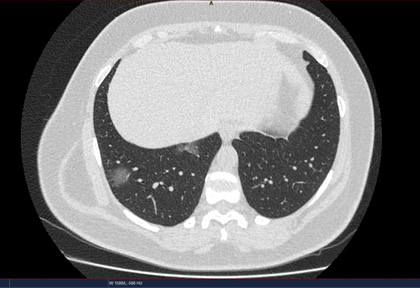

Routine clinical laboratory assays were performed in the hospital’s clinical laboratories. Clinical and laboratory information was extracted from the patients’ medical records. C reactive protein (CRP) in plasma was measured by immunoturbidimetry (Beckman Coulter, Krefeld, Germany). Interleukin-6 (IL-6) levels in plasma were measured by electrochemiluminescence (Siemens Medical Solutions Diagnostics, Siemens Healthcare, Erlangen, Germany). CT scans were read by experienced radiologists who scored results by severity using the criteria shown in Figure 1.

Figure 1. Clinical assessment of pneumonia severity based on computed tomography (CT) scores.

Scoring method: Mild (CT-1)—no more than three ground-glass opacities of <3 cm maximum diameter. Moderate (CT-2)—more than three ground-glass opacities; less than 50% involvement by visual assessment. Medium-heavy (CT-3)—ground-glass opacities and pulmonary consolidation; 50-70% involvement by visual assessment. Severe (CT-4)—diffuse ground-glass opacities with or without consolidation; more than 75% involvement by visual assessment.